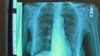

Test reportedly more sensitive than high-tech imaging, especially for distinguishing benign tumors from cancerous ones

Estimated 150 to 185 million people worldwide infected with hepatitis C and many don’t know it